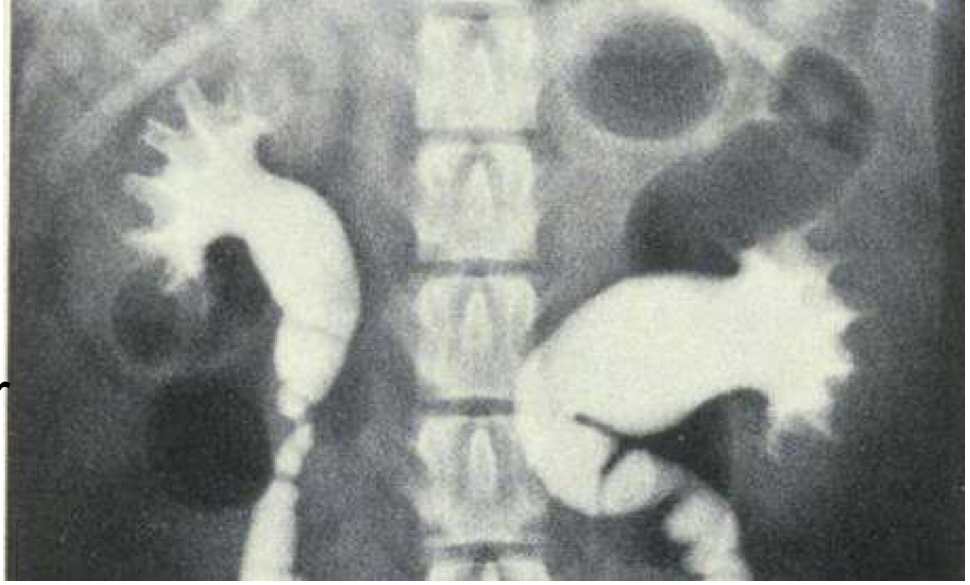

A 5 year old male cat is brought in for an exam because the owner notices him going to the litter box frequently. He also hasn’t been eating and seems lethargic for the past couple days. On exam, the urinary bladder is turgid. Xrays are performed. What is your diagnosis?

Bilateral hydronephrosis due to urethral urolith obstruction.